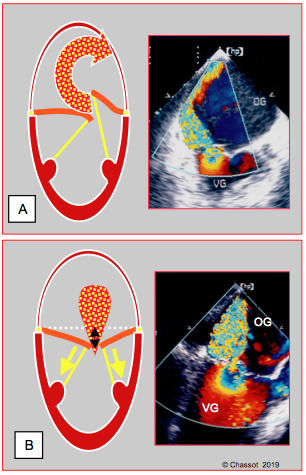

Les oreillettes se retrouvent sous leur ventricule, dans lequel le sang doit monter en diastole. Les pressions auriculaires sont donc plus élevées de 60-150% par rapport aux pressions télédiastoliques ventriculaires correspondantes [10] ; elles doivent le rester pour assurer un remplissage adéquat des ventricules [12]. La pression artérielle systémique baisse alors que la pression artérielle pulmonaire (PAP) augmente. A l'échocardiographie, la taille des oreillettes devient plus grande que celle des ventricules (voir Figure 10.3) [4,10].

Figure 10.3 : Changement de volume de l'OG et du VG lorsque le coeur est verticalisé. A. Vue ETO 2-cavités à 90° du coeur dans sa position normale. La taille de l'OG est environ le tiers de celle du VG. B. Sans modifier la position de la sonde d'ETO, le coeur a été placé en position verticale pour intervenir sur sa paroi postérieure. Les dimensions relatives de l'OG et du VG se sont inversées. L'OG, qui est sous le VG, est plus grande que le VG dont le volume a diminué de moitié.